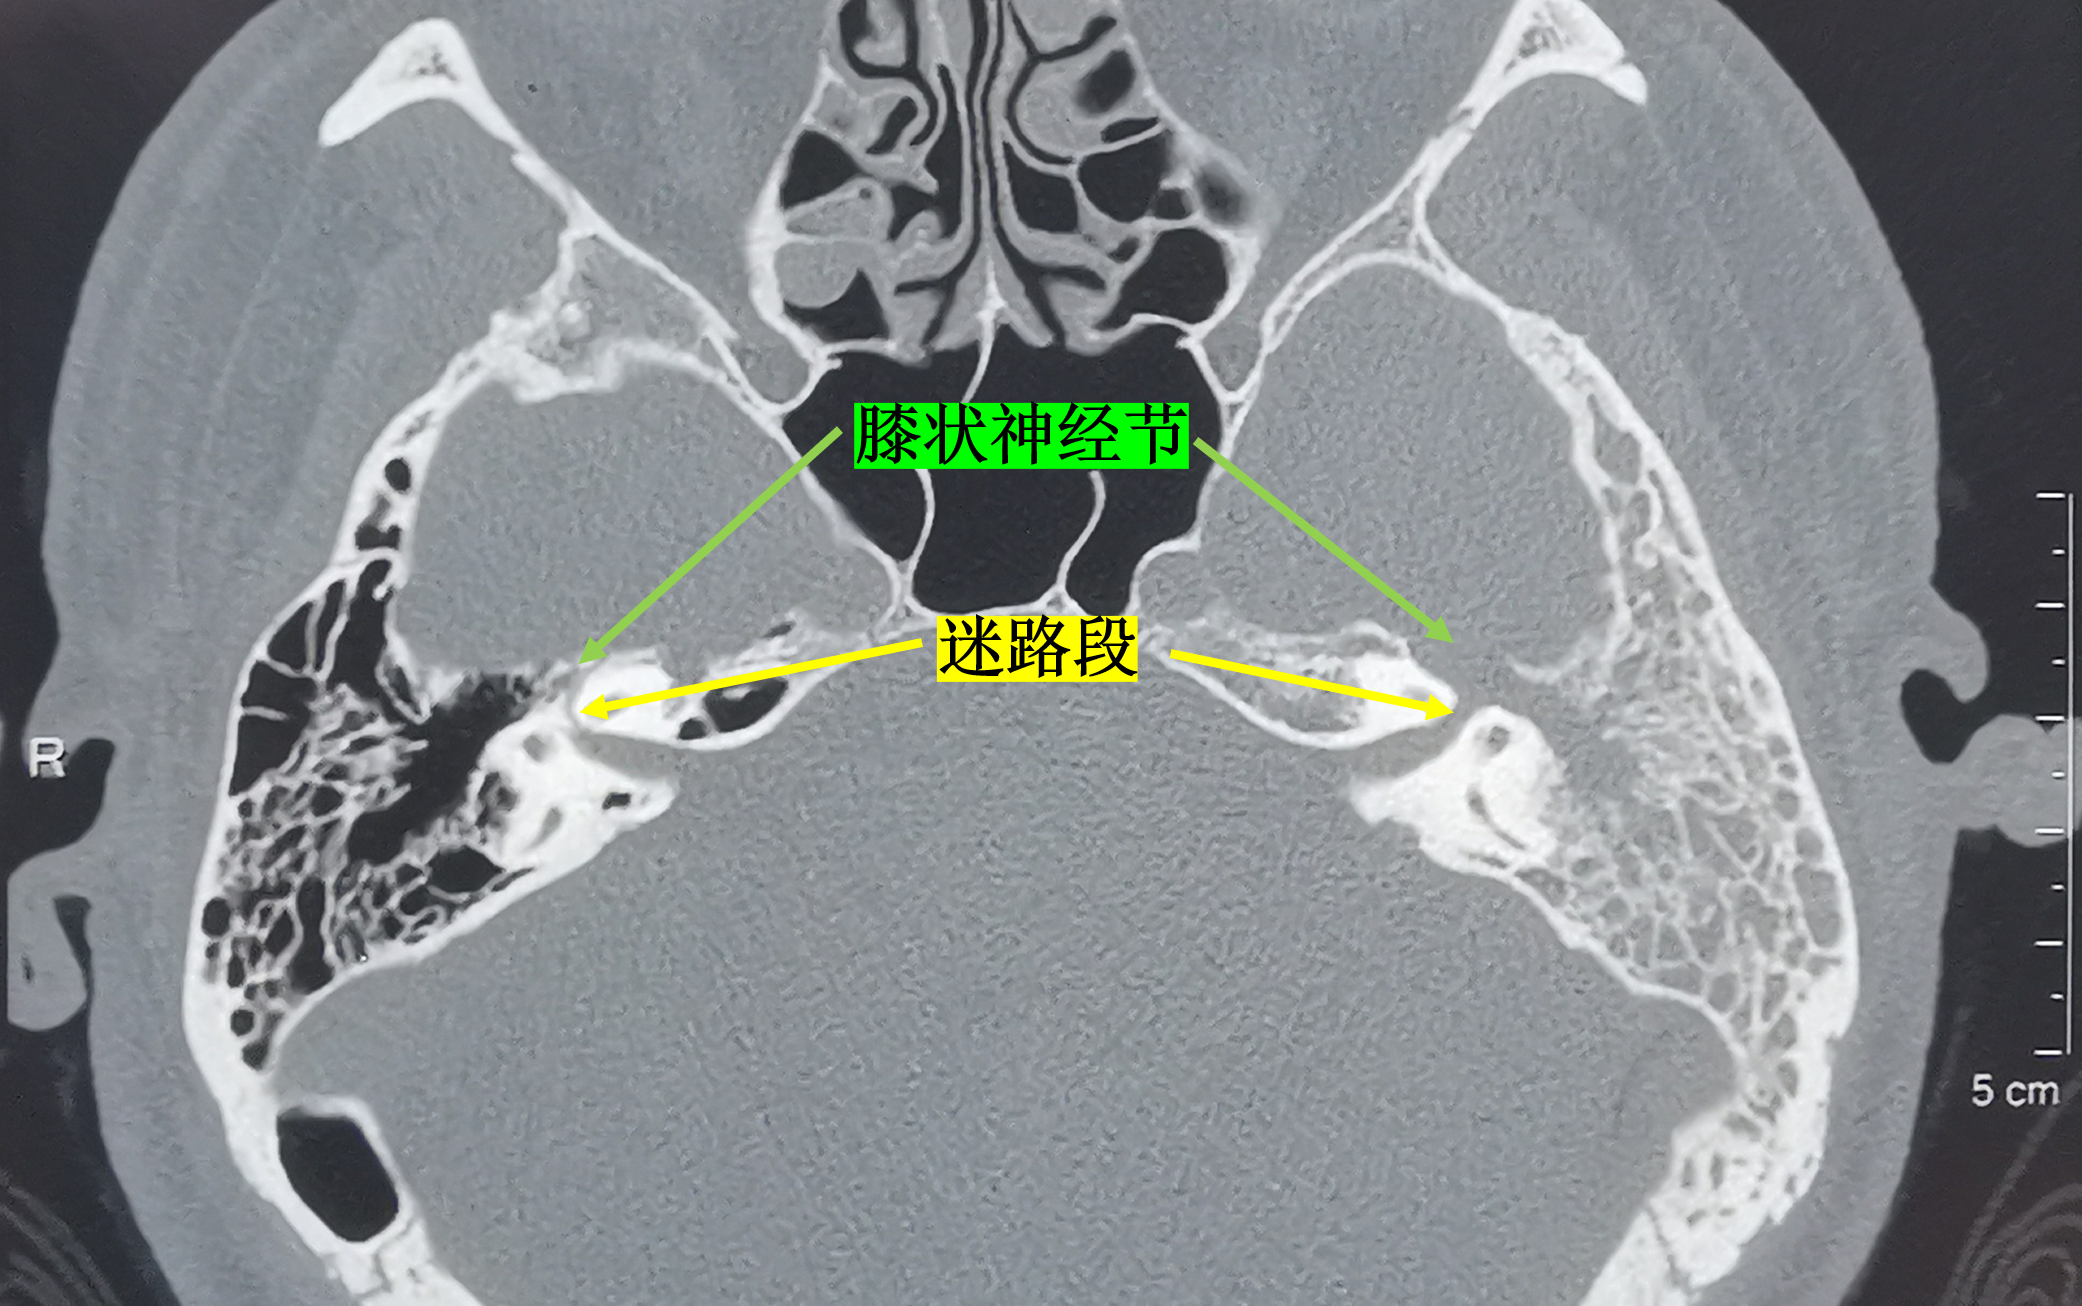

病例4:ct示病变累及面神经膝状神经节,鼓室段,乳突段,向内达颞骨岩部.

图片尺寸2082x1306